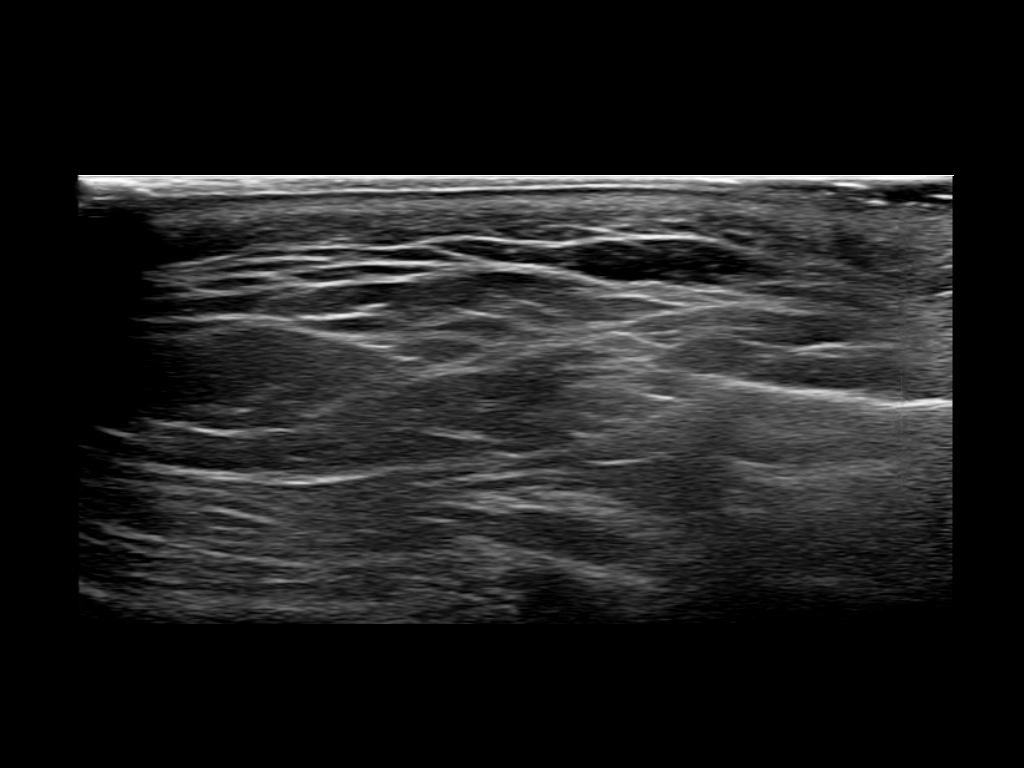

Filler behavior - Temple zygoma US

Study the first image to recognize the different layers. If you are sure about the layers, swipe to the second image to view the answer (if applicable).

Hover over an image to view the secondary image or click on the image title for more information.